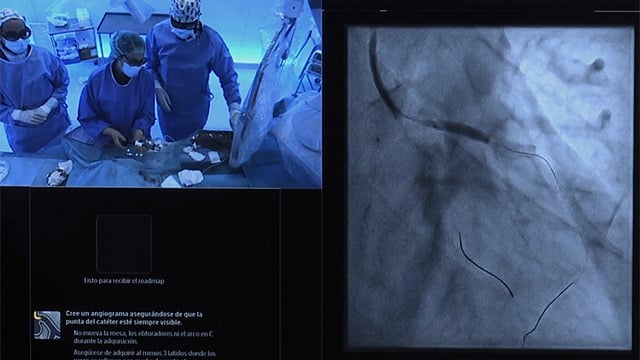

Mitral valve intervention in complex scenarios - Valve-in-valve, valve-in-ring, valve-in-MAC

21 Nov 2023 – From PCR London Valves 2023

What role does imaging play in complex mitral interventions such as valve-in-valve, valve-in-ring or valve-in-MAC? Study how CT-scan, fusion imaging, TEE and TOE are used throughout the procedures and analyse the latest trial results on the subject to get an idea.